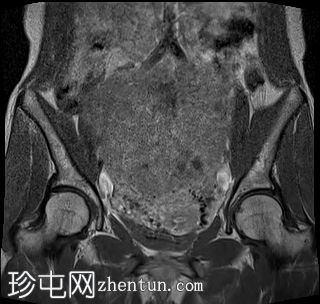

子宫后壁可见一个边界清晰、体积较大的浆膜下肌瘤,大小约为16.1 x 10.5 x 14.4 cm(宽 x 深 x 高)。

该肌瘤在T1加权像上呈中等信号,在T2加权像上呈低信号,内部区域呈囊性变性。

该肿块导致正常子宫结构严重变形。增强扫描显示轻度不均匀强化,未见弥散受限征象或提示恶性肿瘤的可疑强化。

此外,子宫后壁可见多个小型子宫肌瘤,位于肌壁内和浆膜下,无任何退化征象。